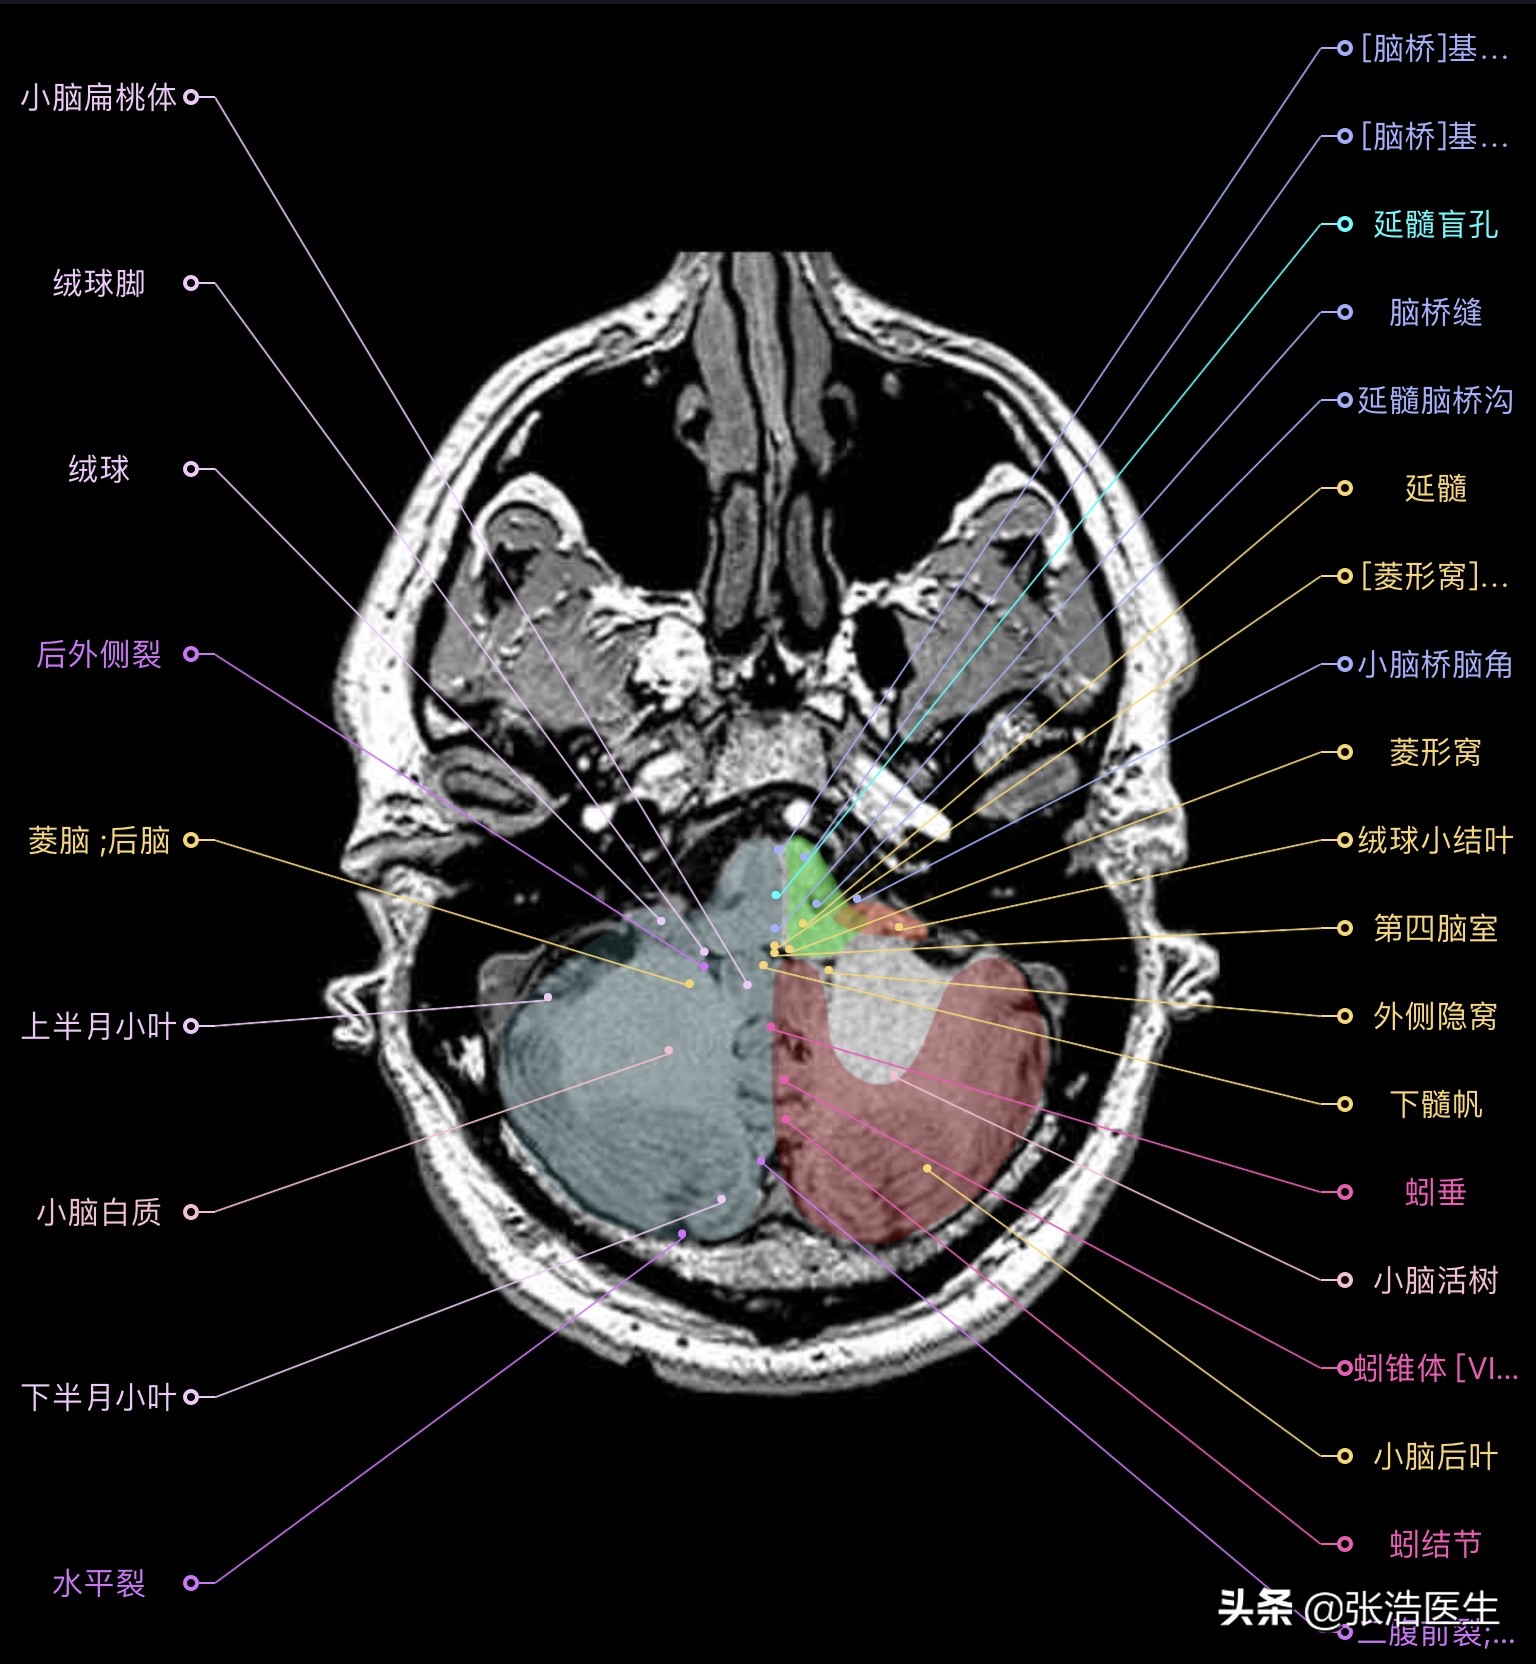

颅脑MRI横断面高清解剖图谱

精选12层常用解剖断面

每一层都带有详细标注,值得收藏学习!